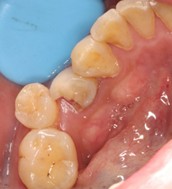

Preoperative Images

May 4, 2025: Extraction of the affected tooth.

Immediate implant placement (first-stage surgery) was performed right after tooth extraction.